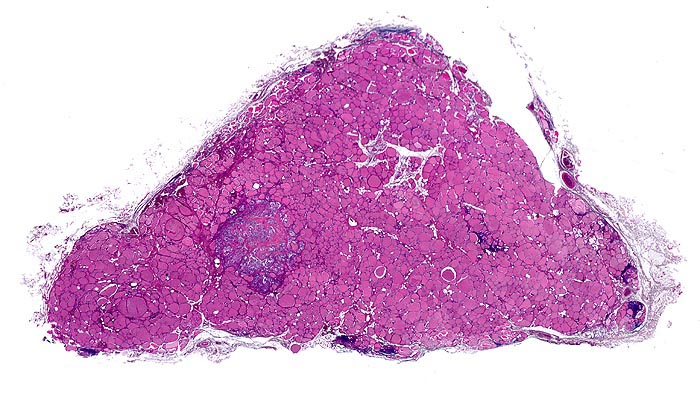

medulläres Schilddrüsenkarzinom bei MEN 2A

Unauffälliges Schilddrüsenparenchym mit spärlichen Entzündungsinfiltraten und einem relativ scharf begrenzten Tumorknoten.

Mehrere scharf begrenzte weisse Knoten in beiden Schilddrüsenlappen von bis zu 8mm Durchmesser.

Beim Vater der Patientin wurde ein bilaterales Phäochromozytom diagnostiziert und in der Folge eine multiple endokrine Neoplasie vom Typ 2A. Im Familienscreening wurde bei der Patientin eine Mutation im Ret-Protoonkogen nachgewiesen und eine prophylaktische Thyreoidektomie durchgeführt.